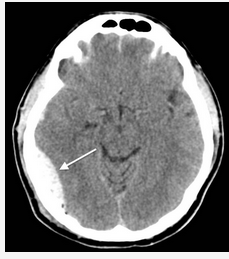

This is a typical case of an epidural hematoma. Unlike the more common subdural hematoma, which is usually due to slow venous bleeding, epidural hematomas are typically due to disruption of the middle meningeal artery, which leads to blood accumulation at arterial pressure. The classic syndrome associated with epidural hematoma includes initial loss of consciousness followed by a short lucid period when patients are often confused and, finally, lose consciousness as the blood exerts enough pressure on the brain to compress brainstem structures.

The blood collection shows the classic biconvex hematoma (Figure 2). Although this syndrome is commonly taught in medical school using pediatric cases as the example, it can be overlooked in older patients and represents a missed opportunity for timely treatment.

A 37-year-old man with a history of alcohol use disorder is in an altercation in a bar and falls down a flight of stairs. He initially gets up from the base of the stairs and sits down. Approximately 6 min after the initial fall, he becomes unresponsive. The emergency medical service is called, and he is transferred intubated to the ICU. After emergent CT scanning (Figure 1), the patient is found to be hypertensive, with a BP of 180/72 mm Hg, tachycardic to 115/min, and breathing spontaneously with pressure support ventilation. On neurological exam, he is poorly responsive to painful stimulus, with flexor posturing on the right side and localization on the left side. The next appropriate treatment is which of the following?